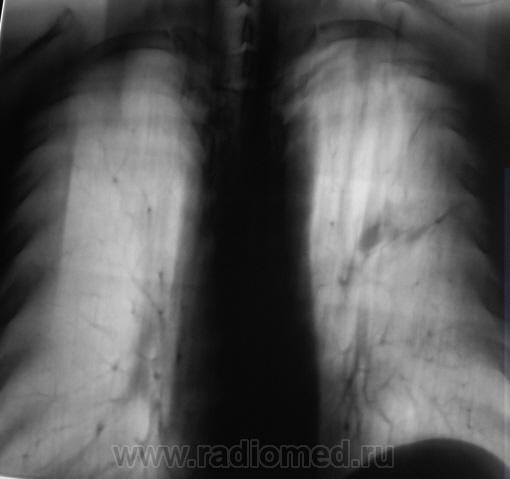

При расшифровке флюорограмм пациент "взят на контроль". Жалоб пациент не предъявляет. Подняли "архив", флюорограмма за 2009 г. - "норма".

Произвели стандартное дообследование.

tbc

А, какой ТВС?